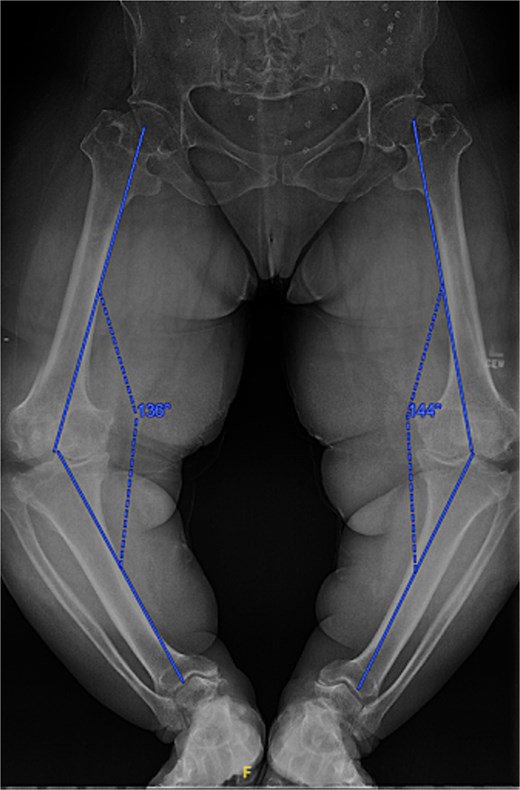

A 61-year-old woman with a history of achondroplasia, gastroesophageal reflux disease, depression, and sciatica presented with progressively worsening bilateral knee pain, mechanical symptoms, and significant difficulty with ambulation. The patient had a body mass index (BMI) of 41.1 kg/m2 and a characteristic short-limb SD phenotype consistent with achondroplasia. On physical examination, the patient demonstrated bilateral varus alignment of the lower extremities and gait assessment revealed a significant varus thrust and valgus instability in mid-stance. Bone length radiographs revealed severe medial joint space narrowing, metaphyseal flaring of the tibia and femur, and bilateral mechanical axis varus deformity measuring 36 and 44 degrees on the left and right legs, respectively (Fig. 1).

Preoperative standing AP radiographs demonstrating severe bilateral mechanical axis varus deformity measuring 36 and 44 degrees on the left and right legs, respectively.